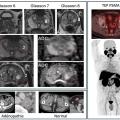

Perspectives en imagerie médicale oncologique

Le dépistage, le diagnostic et la prise en charge des cancers les plus fréquents, tels que le cancer du sein, de la prostate, du poumon et colo–rectal, reposent sur des avancées majeures en imagerie médicale. Grâce à des techniques performantes comme la mammographie, l’imagerie par résonance magnétique (IRM) multiparamétrique, la…

Avancées et intégration de la médecine nucléaire dans la pratique clinique

La médecine nucléaire, spécialité d’imagerie médicale en plein essor depuis cinquante ans, joue aujourd’hui un rôle important dans de nombreuses spécialités, telles que l’oncologie, la cardiologie ou encore la neurologie. Le principe de la médecine nucléaire repose sur l’utilisation de sources radioactives non scellées pour…